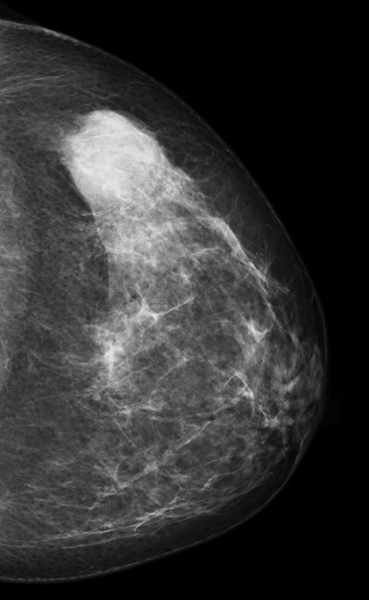

Tumeurs du sein - Cancer nodulaire chez une femme de 30 ans

Mammographie, masse externe gauche, contours estompés BIRADS 4.